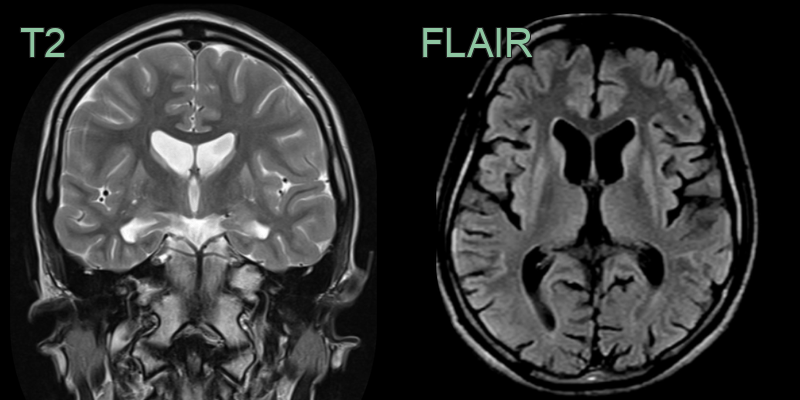

- A 55-year-old patient with a history of depression presented after worsening incoordination.

- Imaging showed marked atrophy of the caudate head. There was less pronounced atrophy of the T2-hyperintense putamina.